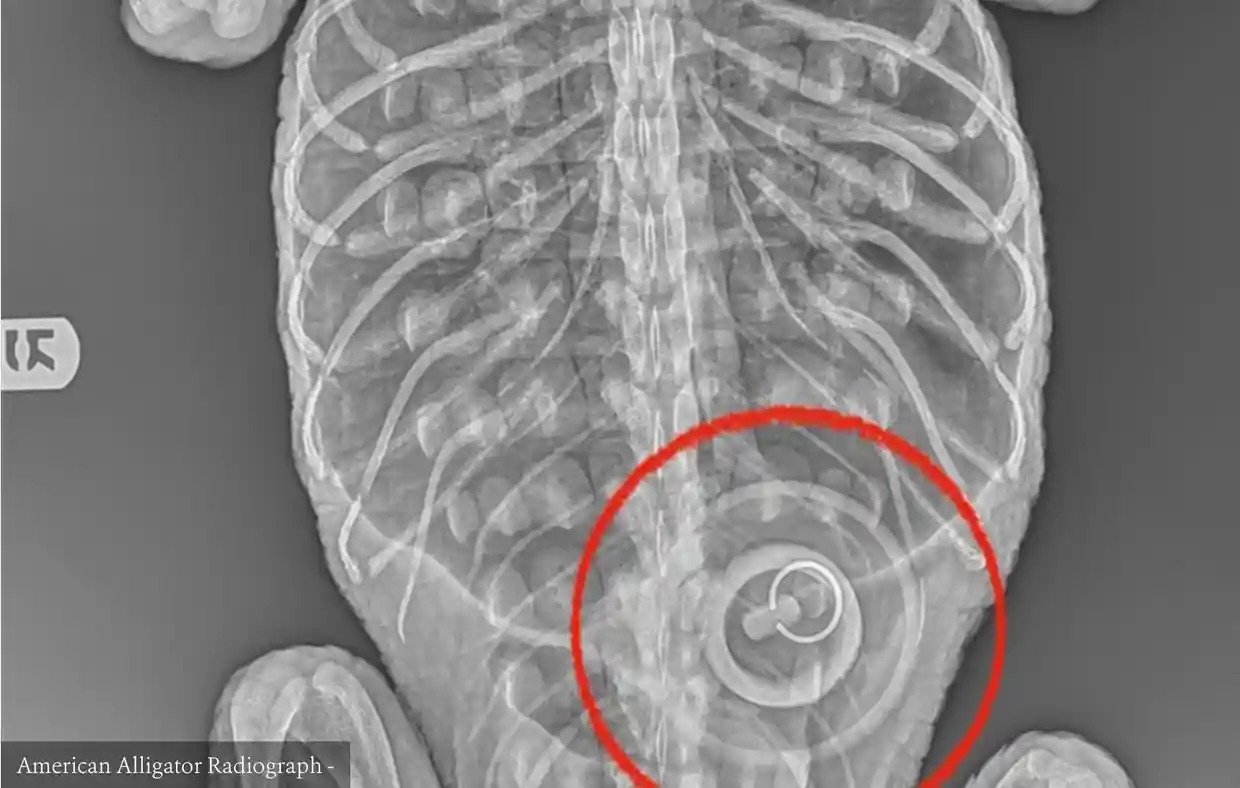

Hiệp hội Bảo tồn Động vật Hoang dã của Mỹ cho biết họ phát hiện một nút chặn bồn tắm rộng hơn 10 cm mắc kẹt trong bụng con cá sấu được giải cứu từ công viên tại Brooklyn gần đây.